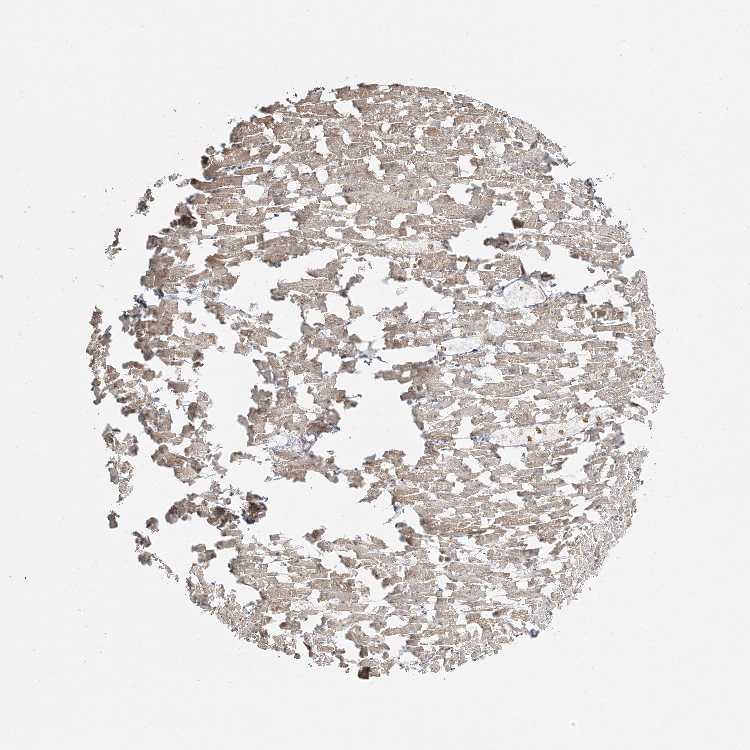

HEART MUSCLE - Antibody stainingi

Antibody staining in the annotated cell types in the current human tissue is reported as not detected, low, medium, or high, based on conventional immunohistochemistry profiling in selected tissues. This score is based on the combination of the staining intensity and fraction of stained cells.

Each image is clickable and will lead to virtual microscopy that enables deeper exploration of all samples and also displays staining intensity scores, fraction scores and subcellular localization as well as patient and tissue information for each sample.

Antibody HPA035863

Cardiomyocytes Medium